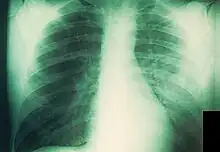

La peste neumónica tiene dos formas, primaria y secundaria, frecuentemente mortales y potencialmente contagiosas para los contactos cercanos.[48][49] Es más común la secundaria, causada por la diseminación hematógena de la bacteria desde el bubón u otra fuente. Aproximadamente el 10 % de los enfermos de peste en los Estados Unidos desarrollan peste neumónica secundaria, habitualmente por el retraso en el tratamiento de la forma bubónica. Comienza como un proceso intersticial con tos productiva y esputo escaso, que normalmente comienza cinco o seis días después de los primeros síntomas. La radiografía de tórax revela infiltrados alveolares difusos casi siempre bilaterales y acompañados de derrame pleural.[50] Sin tratamiento, el esputo se vuelve más copioso y, finalmente, sanguinolento; la muerte ocurre frecuentemente a los tres o cuatro días.[4]

La forma primaria de la peste neumónica es un cuadro fulminante que resulta de la inhalación directa de la bacteria en los pulmones. Puede ocurrir al haber estado en contacto con otra persona con peste neumónica, exposición a animales con peste respiratoria o faríngea (especialmente gatos), infección en el laboratorio o, potencialmente, consecuencia de la liberación intencional de aerosoles con propósitos terroristas. Los síntomas comienzan entre uno y cuatro días después de la exposición; se instauran velozmente e incluyen fiebre, escalofríos, cefalea, malestar, signos generales de endotoxemia, taquipnea, disnea, hipoxia, dolor torácico, tos y hemoptisis. La radiografía de tórax muestra al principio una neumonía lobar que evoluciona a una consolidación densa y diseminación broncopulmonar a otros lóbulos del pulmón ipsilateral o contralateral.[36][51] Normalmente, el esputo es purulento, aunque también puede ser acuoso, espumoso y copioso; asimismo, es posible que presente algo de sangre o que sea francamente hemorrágico, en cuyo caso podría contener grandes cantidades de bacilos.[48] En cuanto a la histología, el espacio alveolar se muestra lleno de bacterias y células inflamatorias.[43] La enfermedad casi siempre es letal sin tratamiento y la mortalidad es también alta cuando este se demora más de 24 horas tras el comienzo de los síntomas. Más o menos, el 25 % de los afectados por peste neumónica en los Estados Unidos desde 1950 han fallecido.[4]